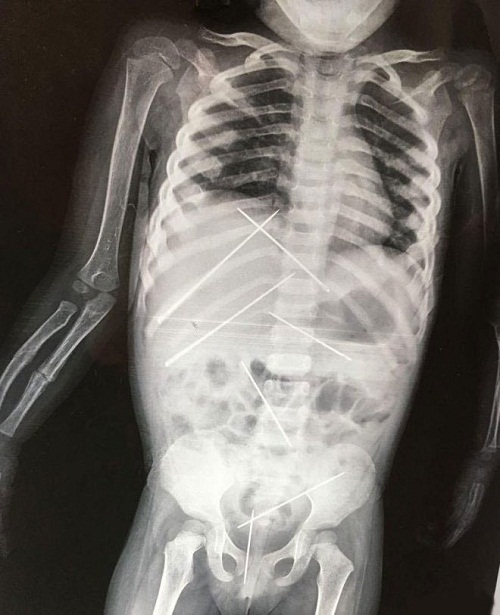

Qua kiểm tra và tiến hành chụp X-quang, các bác sĩ đã sốc khi phát hiện 7 cây kim dài 5 cm găm vào bụng của cô bé. Thậm chí, Goswami còn bị gãy một cánh tay.

| Kết quả chụp X -quang cho thấy có 7 cây kim găm vào bụng cháu gái |